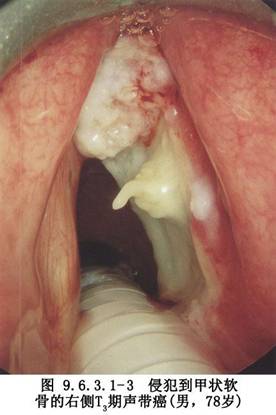

声门上癌 ①t3~t4;②声带已固定;③会厌室带癌并侵犯声带;④侵犯